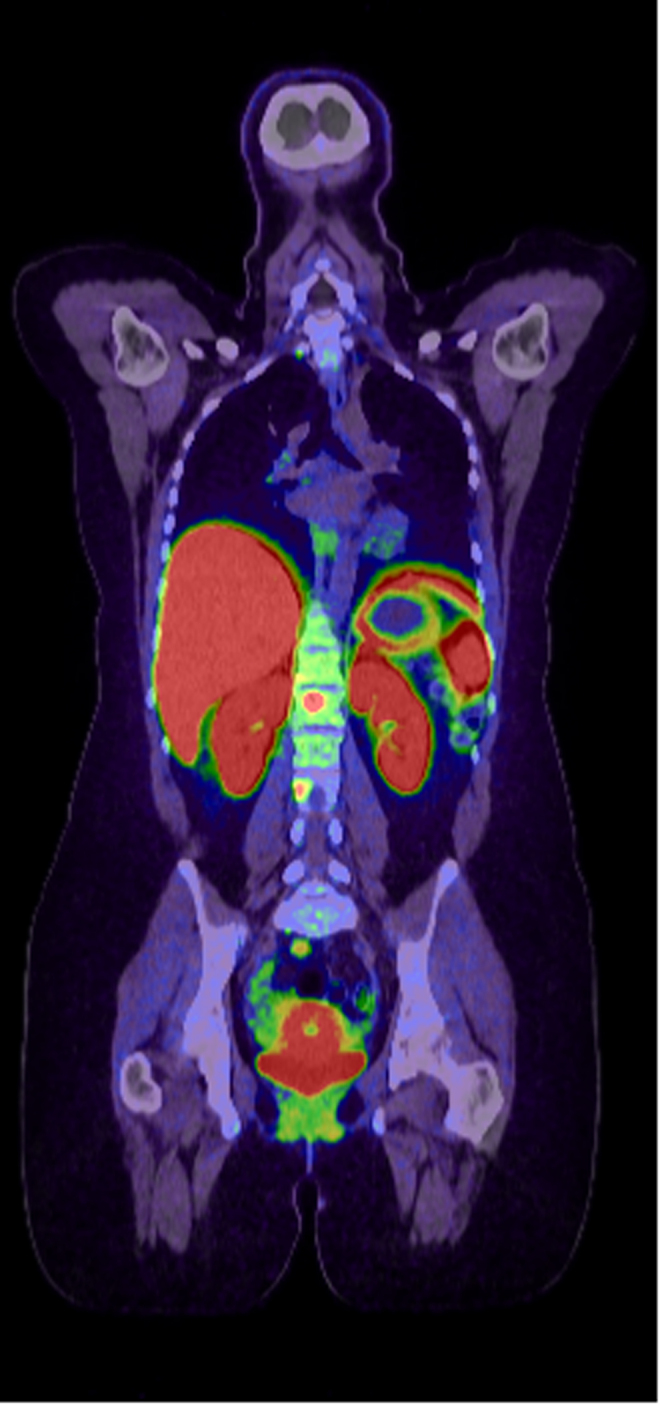

Summary: Pregnancy in the setting of metastatic paraganglioma is challenging, particularly in the context of tyrosine kinase use. We describe a 26-year-old female with a background of metastatic paraganglioma harboring a pathogenic SDHB variant, requiring sunitinib, which was withheld to facilitate the safe conception and delivery of a healthy baby. She required no alpha- or beta-blockade during her pregnancy and exhibited no signs of tumor progression or symptoms throughout this period. Historically, higher rates of fetal and maternal morbidity and mortality have been experienced in the setting of pregnancy. Although limited data exist on the management of metastatic paraganglioma in pregnant patients, this case suggests that careful treatment modifications, such as temporary tyrosine kinase therapy cessation and vigilant monitoring, can result in successful pregnancies without compromising maternal or fetal well-being.

Learning points: Paraganglioma in pregnancy has been associated with poor fetal and maternal morbidity and mortality. Many of the treatment modalities for metastatic paraganglioma, including tyrosine kinase inhibitors, can affect fertility or cannot be utilized in pregnancy, necessitating the temporary suspension of these treatments. This case exemplifies that careful clinical and biochemical monitoring during pregnancy is required to avoid maternal and fetal harm while balancing the risk of disease progression off treatment.